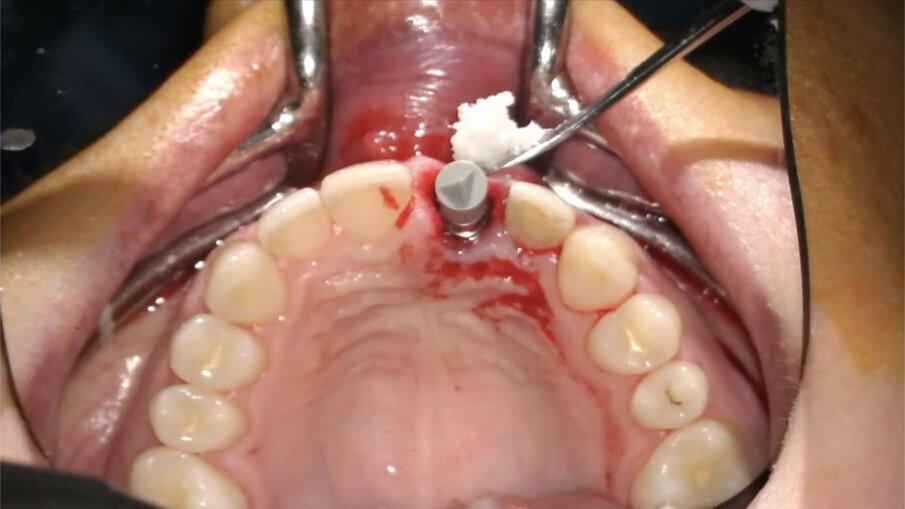

L’impianto (XIVE – Dentsply Sirona) è stato posizionato centralmente con un’inclinazione palatale al fine di evitare che il foro di accesso della vite cadesse sul margine incisale del provvisorio o, ancor peggio, sulla sua superficie vestibolare. Il gap osseo vestibolare è stato riempito con Geistlich Bio-Oss (Geistlich Pharma) (Figg. 16-19).

Fig. 16_Inserimento dell’impianto Xive FX 3.8.

Fig. 17_Posizione corretta dell’impianto post-estrattivo.

Fig. 18_Posizionamento del biomateriale.

Fig. 19_Gestione del biomateriale.